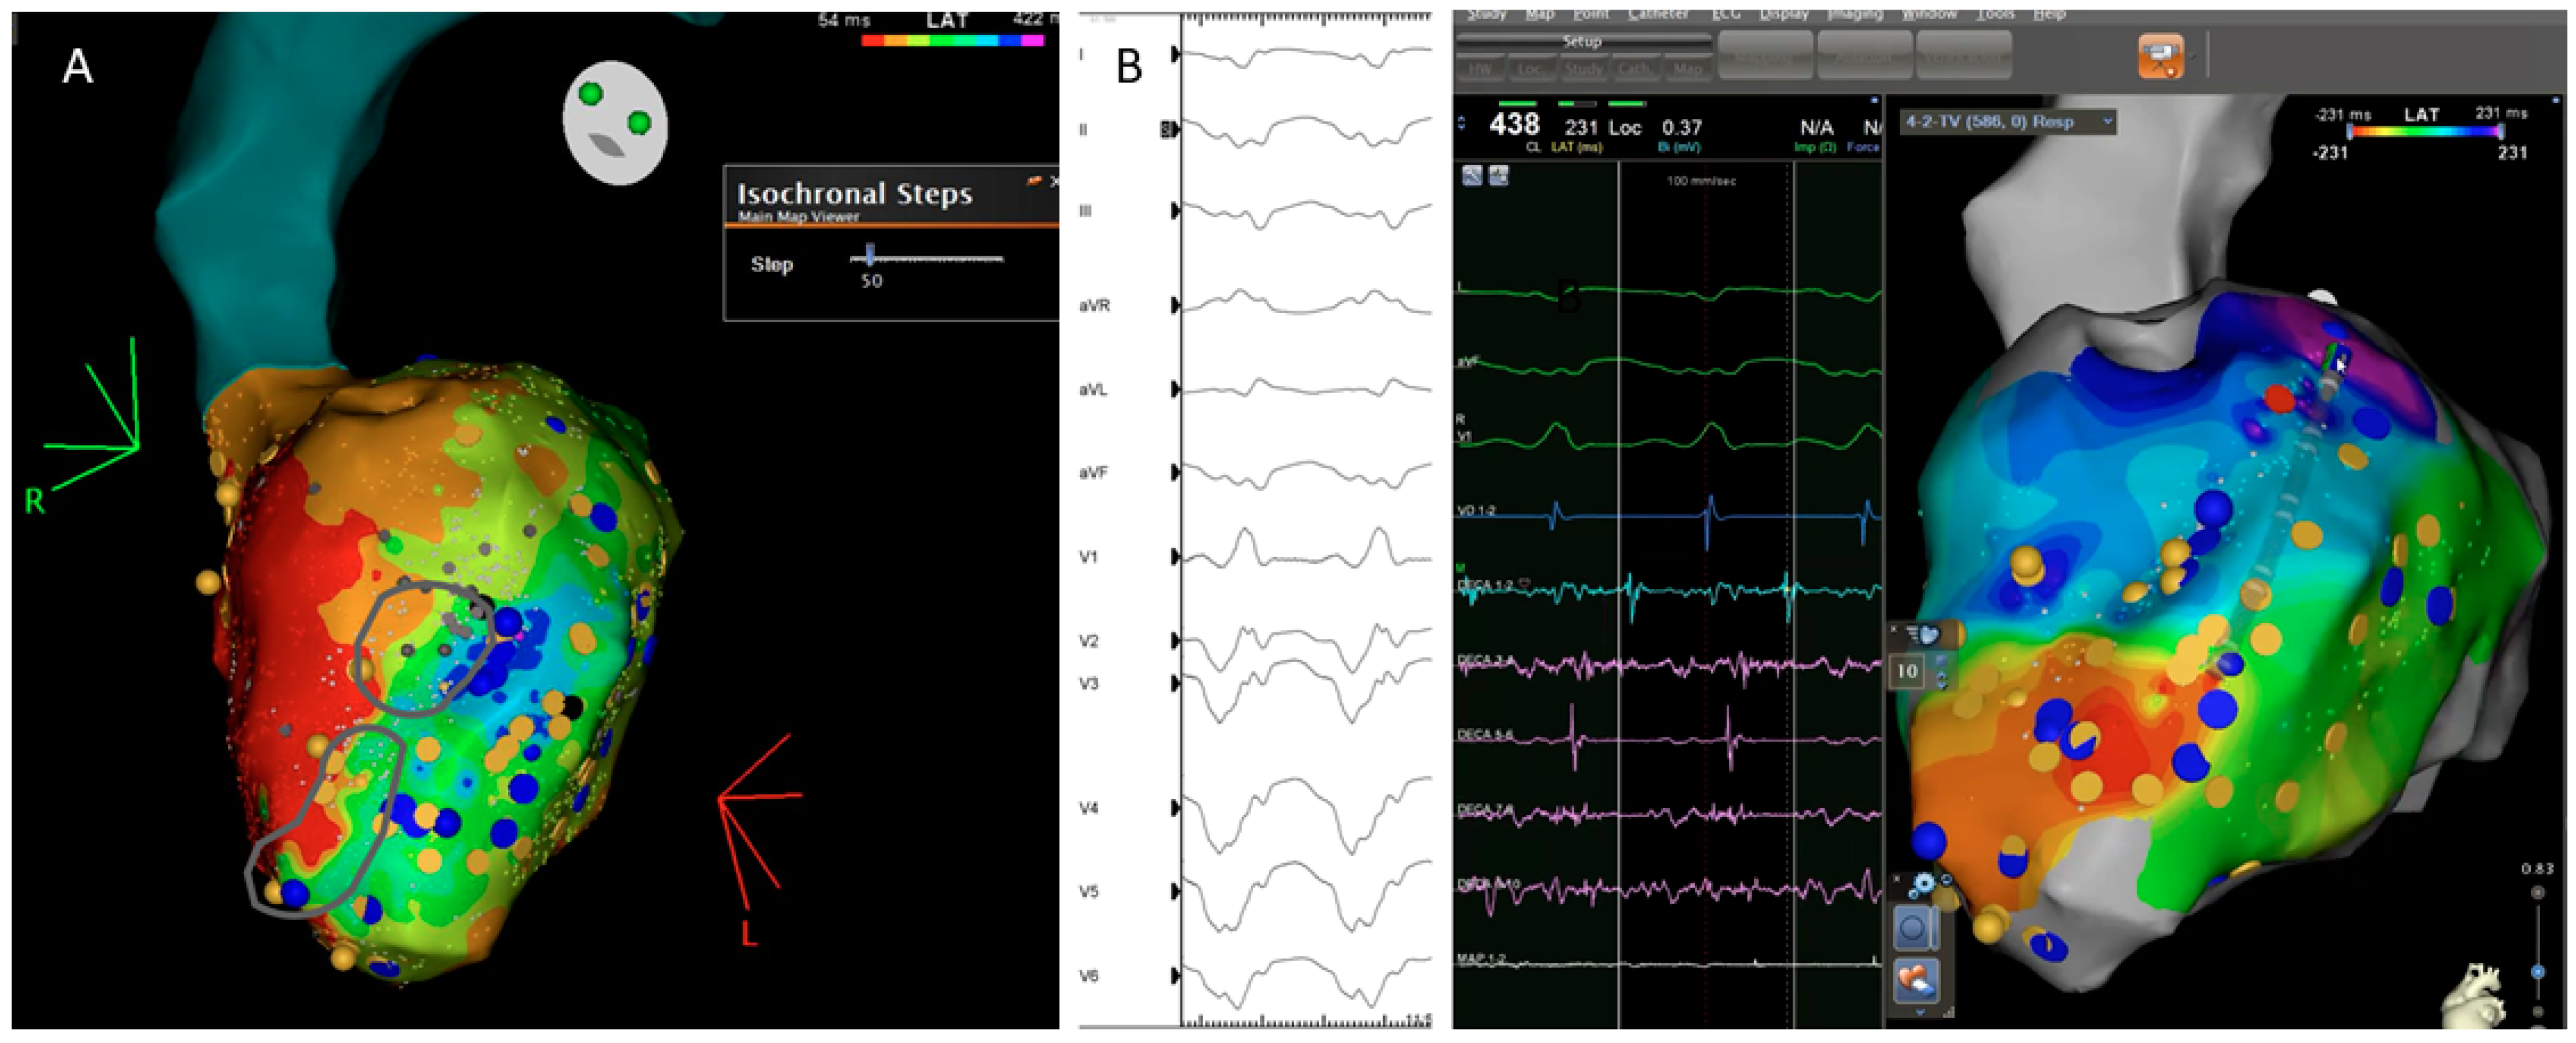

3.6. PHYSIO-VT

3.7. Isochronal Late Activation Mapping (ILAM)

| PHYSIO VT | ANTER 2020 | 85 ischemic. | RHYTMIA 92.8% CARTO 7.2% | -SR and RV Pacing 600 ms and LV Pacing 600 ms | Area of activation maps (isochronal maps of 10 ms steps) | To compare areas of activation slowing and critical VT isthmus in three different maps (SR, RV and LV) | Acumulative area of activation slowing | 27.7 | The direction of LV activation is influenced by the magnitude and location of activation slowing: SR Mapping identify 66.2% of the entire area of activation slowing. RV and LV unmask an additional 33% |

| ILAMS | AZIZ 2019 | 120 patients: 50% ischemic | Ensite Precision | Annotation of last deflection and division of the total activation window in 8 equal isochrones | Deceleration zones (DZ): 3 isochrones in less than 1 cm. | To correlate DZ with VT isthmus | Primary DZs | 29 | DZs identify during SR are strongly predictive of critical sites for reentry. |